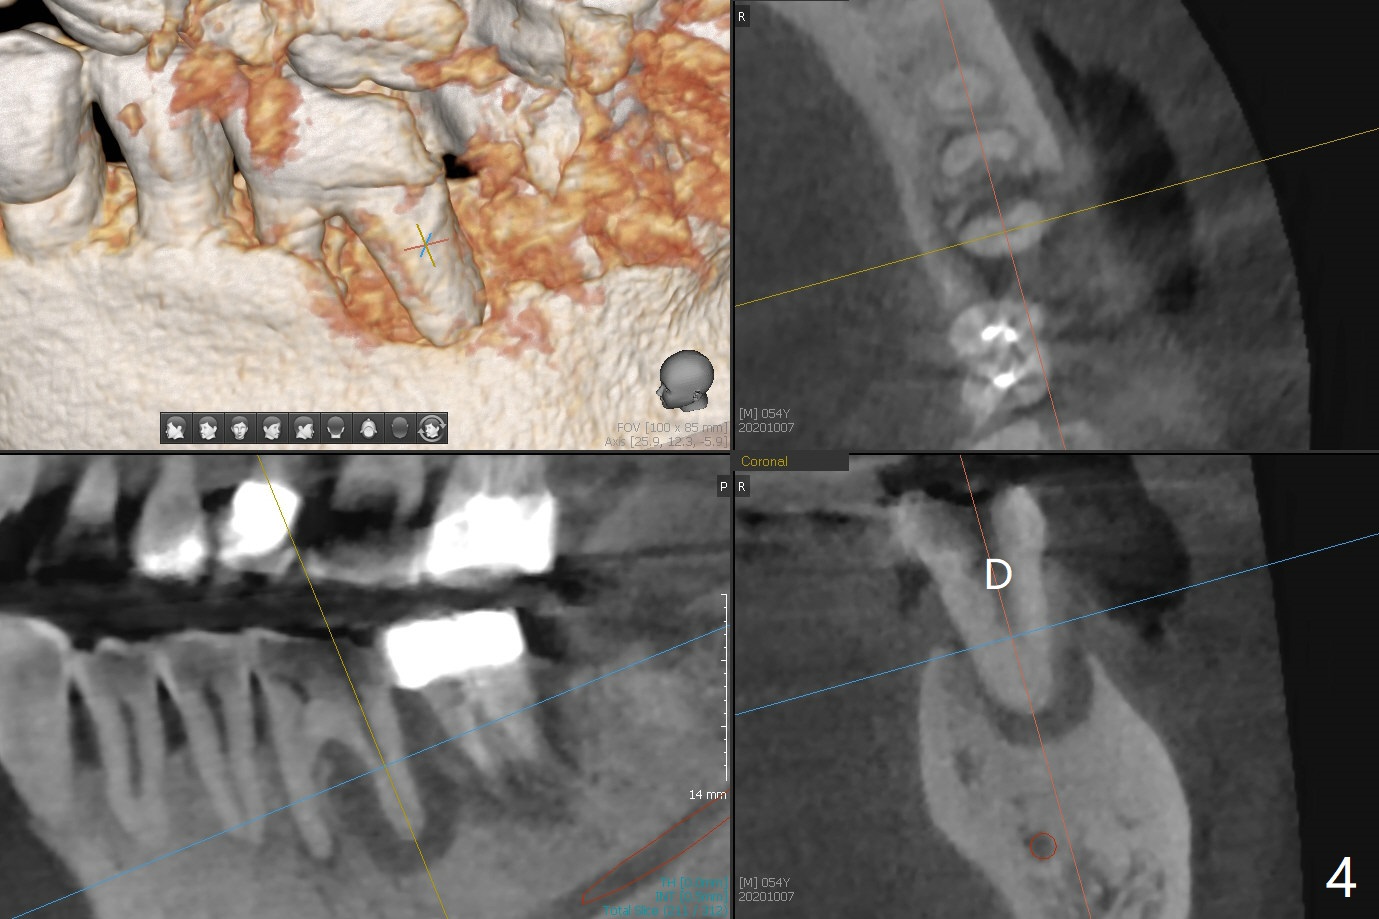

54岁男牙齿问题好像与牙周病和咀嚼力大有关(图一),虽然右上3(图二)和左下6(图三,四)需要治疗,因为疼痛他要求先处理左上6(图五)。后者腭侧根骨质吸收严重,植体尽量颊侧植入(图六),4.5 或者5.0x11毫米。放置粘性骨粉至植体平台,为了简化术中基台放置,使用Non-Hex Temporary Abutment,临时牙冠做的尽量大,占据牙槽窝空间,最后将PRF膜塞入两者之间。Return to Prevent Molar Periimplantitis (Protocols, Table) No Deviation No Caries Metronidazole CT/前牙植牙 Socket Shield Xin Wei, DDS, PhD, MS 1st edition 10/11/2020, last revision 02/21/2021